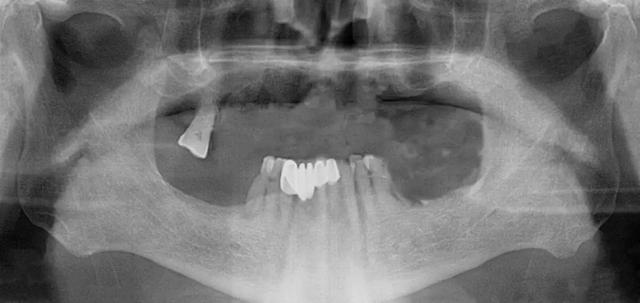

家住安丘的郎先生,因上牙床僅剩一顆牙齒,吃飯很受影響。在了解到濰坊市中醫(yī)院口腔科種植全口牙當天可以接著戴牙吃飯,慕名來找李德仁主任尋求幫助。

口腔科李德仁主任為老人仔細檢查了口腔情況,由于缺牙時間太久,牙床骨量極少,正常的種植修復需要植骨,手術創(chuàng)傷大而且半年后才能鑲牙吃飯。建議他進行數(shù)字化導板種植,可以不用植骨而且當天就能戴牙吃飯,手術簡單,創(chuàng)傷小。老人和孩子很信任的接受了李主任的種植方案:上牙床種植5顆,下牙床種植4顆,當天戴牙吃飯。